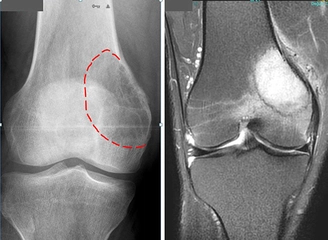

Tanı YöntemleriAkciğer tümörü tanısı, hastanın belirtileri ve fiziksel muayenesi ile başlayarak çeşitli testler ile devam eder. Tanı yöntemleri arasında: